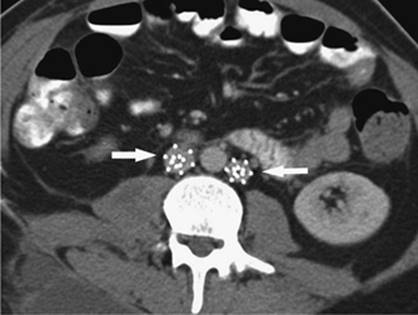

Figure 35.22. Attempted canalization of the portal vein during a transjugular intrahepatic, portacaval shunting (TIPS) procedure. This CO2 injection identifies canalization of the hepatic artery (black arrow).